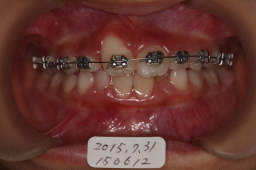

2015年07月31日

約1カ月でほぼ捻転歯が改善。